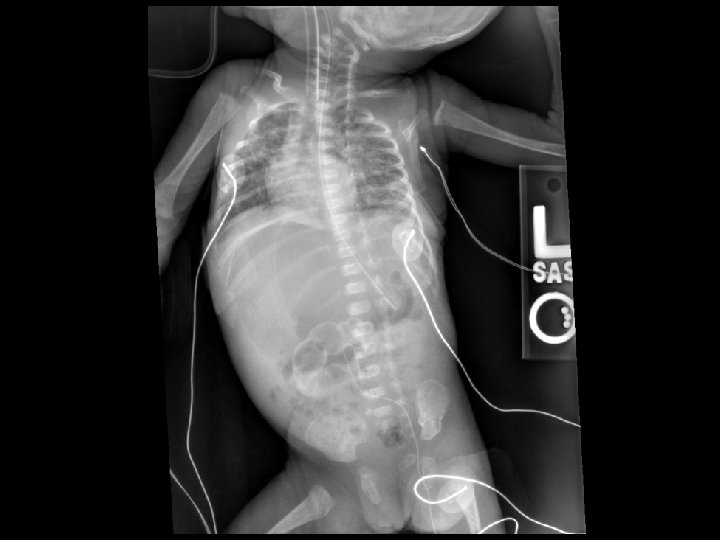

CDH

Congenital Diaphragmatic Hernia: Pathophysiology • Pulmonary hypoplasia: affects both lungs – Pulmonary vascular hypoplasia • Pulmonary artery hypertension • Associated anomalies: cardiac, limb, and syndromes • Tracheobronchial anomalies

Congenital Diaphragmatic Hernia: Delivery Room Management • Place orogastric tube • Limit bag/mask ventilation • Early intubation of infants with respiratory distress • Consider administration of surfactant • Limit peak pressures to < 25 cm H 2 O • Avoid overventilation and overdistention

Congenital Diaphragmatic Hernia: Initial management • • • Vascular access Accept p. CO 2 in the 40’s - 60’s Cardiovascular support: volume, pressors Look carefully for other anomalies Echocardiogram Head ultrasound